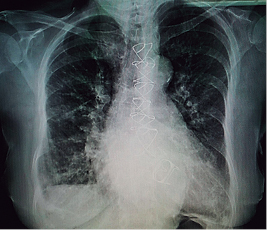

Results of paraclinic studies: surface electrocardiogram of 12 leads in atrial fibrillation rhythm, with posterior right fascicle hemiblock and non-specific repolarization disorders. Chest X-ray in anteroposterior projection where sternal cerclage is observed and right hemidiaphragmatic elevation, apparent cardiomegaly, with both costodiaphragmatic and cardiofrenic angles deleted on right hemidiaphragm, with images of valvular stents suggesting mitral and aortic positions, with increased bilateral vascularity and prominent pulmonary cone (Figure 1). On cardiac tomography with 3D reconstruction, it can be seen the mitral prosthetic valve with 2.33 cm of anteroposterior diameter and 2.39 cm of lateromedial diameter (Figure 2).

Figure 1: Chest X-ray in anteroposterior projection, right hemidiaphragmatic elevation, apparent cardiomegaly, with both costodiaphragmatic and cardiofrenic angles deleted on right hemidiaphragm, suggestive of pleural effusion of 25%, with images of valvular stents in mitral and aortic positions, with increased bilateral vascularity and prominent pulmonary cone.